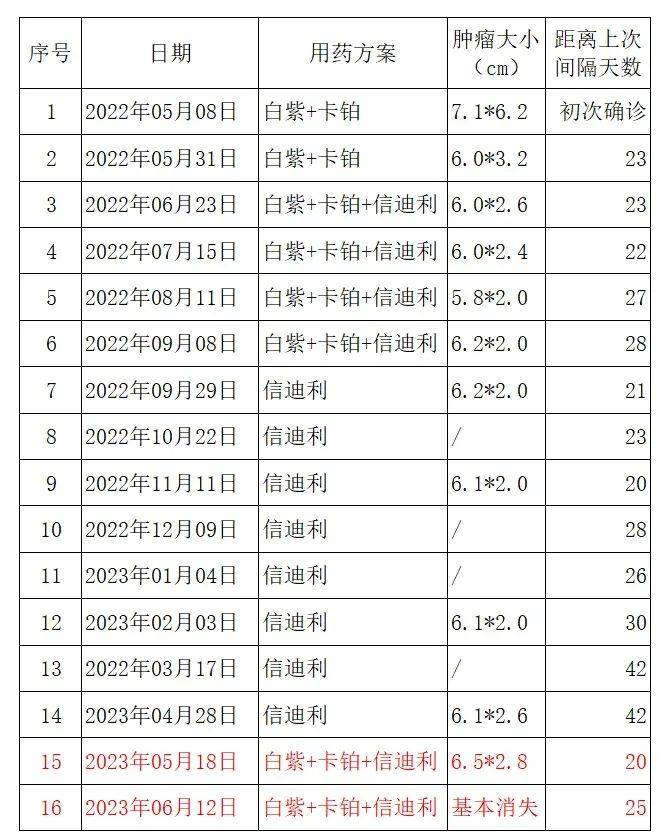

在医生的建议、外加我的多方咨询下,最终采用了化疗联合免疫,后期单免维持,进展复用化疗的方案。经治疗至今,共1年又4个月,肿块基本消失,用药时间、用药方案和肿瘤大小我做了张对比表,详见下图:

图片来源:患者提供